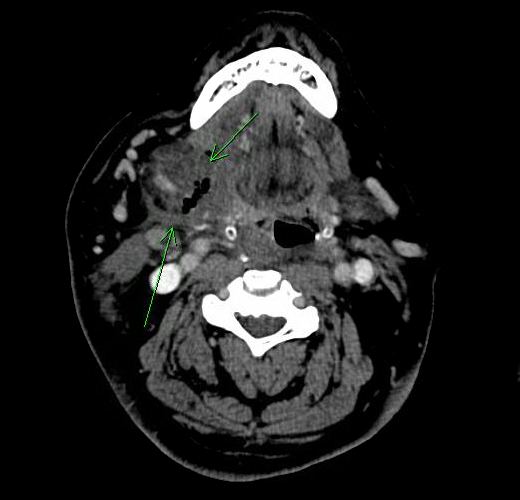

Case Presentation: A 58-year-old male with hypertension, morbid obesity and obstructive sleep apnea (OSA) was shifted to MICU for monitoring of his respiratory status following elective vitrectomy under general anesthesia. He was managed with non-invasive ventilation (NIV) for OSA overnight. Next day he developed an acute onset, right-sided painless neck swelling without associated dysphagia, odynophagia or stridor. Physical examination was remarkable for overlying erythema, mild desquamation without fluctuance or crepitus. Floor of the mouth was tender to palpation. He was afebrile with normal white count. CT scan showed asymmetric enlargement and edema of the right submandibular gland with multiple foci of gas within the gland and surrounding tissues concerning for necrotising fascitis. Empiric antibiotic therapy with vancomycin, piperacillin-tazobactam and clindamycin was started. His clinical course was stable without any features of systemic toxicity. Blood cultures showed no growth after 48 hours so antibiotic therapy was deescalated. A clinical diagnosis of traumatic intubation followed by extravasation of air into the soft tissues as a result of positive pressure non-invasive ventilation was made. Patient was observed for 48 hours with resolution of swelling and erythema.

Discussion: Necrotizing fasciitis (NF) is a microbial infection involving soft tissue, causing disseminated necrosis and eventual systemic toxicity leading to death. Due to its associated high morbidity and mortality, NF should preferably be misdiagnosed rather than being a missed diagnosis. Our patient had an acute onset of right sided swelling with imaging evidence of soft tissue gas, raising concerns for necrotizing fasciitis. The absence of tenderness, fever, leukocytosis and systemic symptoms suggested otherwise. Occult trauma from intubation or irritation form endotracheal tube, complicated by forceful air entry into the interstitium and submandibular space from NIV lead to the described clinical picture.